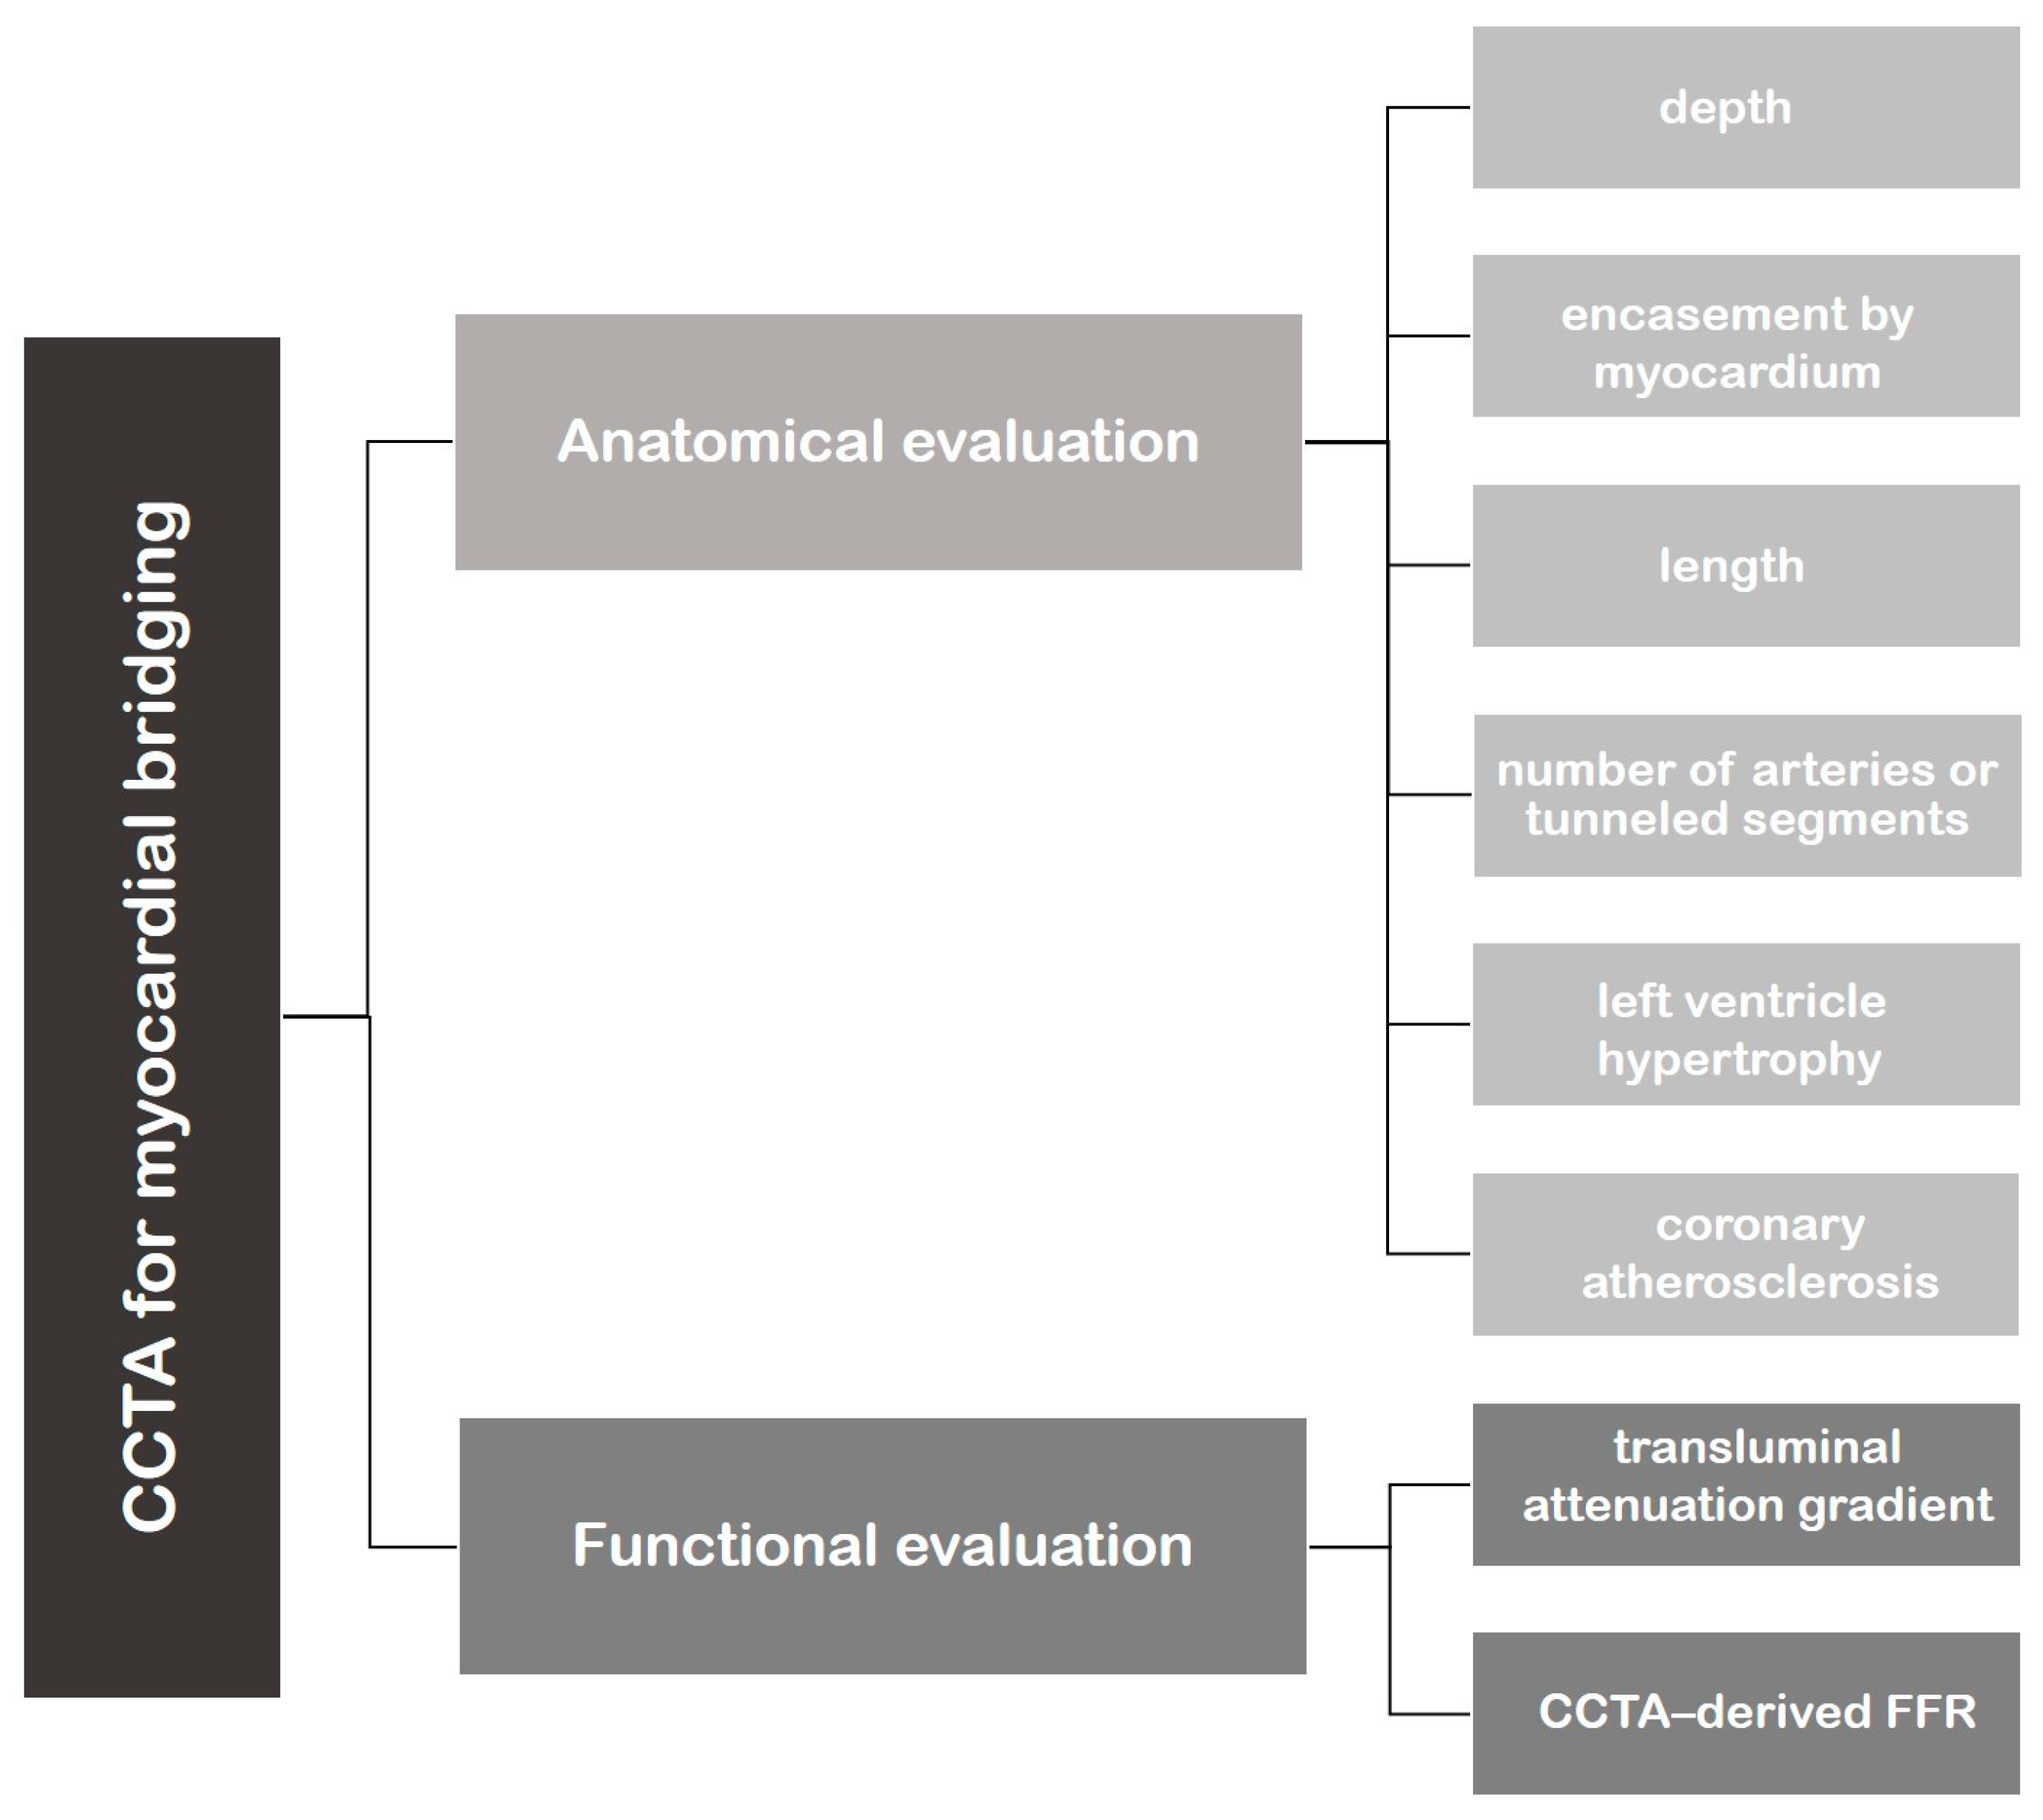

3. Role of CCTA: Anatomical Evaluation

4. Role of CCTA: Functional Evaluation